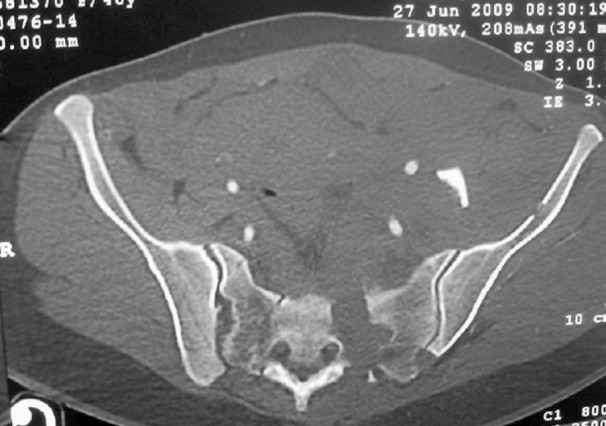

This patient has extensive and complicated skeletal injuries...much more data (such as additional relevant images and clinical information regarding the soft tissues and overall patient status) would help us formulate an informed plan.

The sacral pattern alone is quite difficult and seems to be some version of an H-pattern, but I can’t tell from these films.

General condition is fine except for an intractable pelvic pain, no associated injuries (only ankle fracture), no sciatic nerve injury.

The soft tissues are also in mild condition, buttock hematoma and probably a Morel-Lavalle. I send some more CT images. There are some conminution in the posterior column (I don’t have images now). The patient is scheduled for surgery next Monday. The plan is percutaneous sacral fixation and then ilioinguinal approach .

I am a huge fan of closed reduction and percutaneous posterior pelvic fixation, but that particular sacral injury warrants an open reduction.

I’d begin with that in order to have a high quality osseus foundation for subsequent acetabular repair.